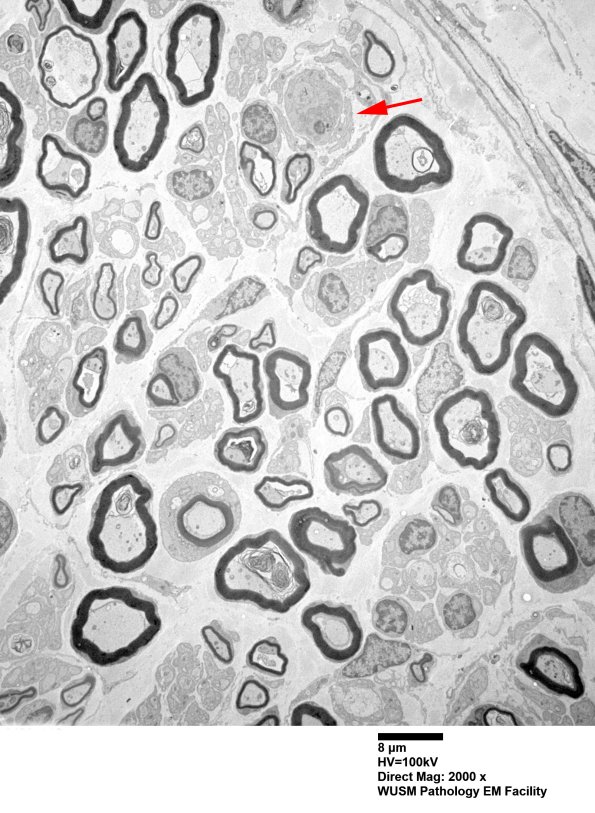

6B3-5 This image shows one particularly photogenic large pre-myelinated axon (arrow, 6B3), seen at higher magnification in the subsequent images. (electron micrographs)